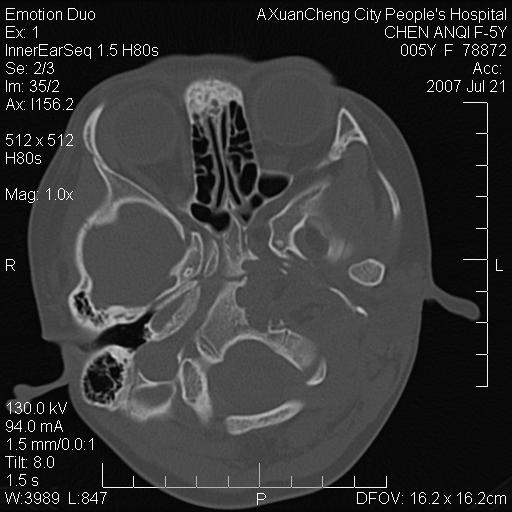

标题: PED0273:5岁,左耳流脓痛疼一周,颅底骨质破坏 [打印本页]

标题: PED0273:5岁,左耳流脓痛疼一周,颅底骨质破坏

患儿5岁,左耳流脓痛疼一周,左外耳道肉芽组织填塞 软组织窗显示病灶内结节状低密度影为气体密度

左侧中耳炎并胆脂瘤,左颞骨岩部骨质破坏并颅内感染积气。